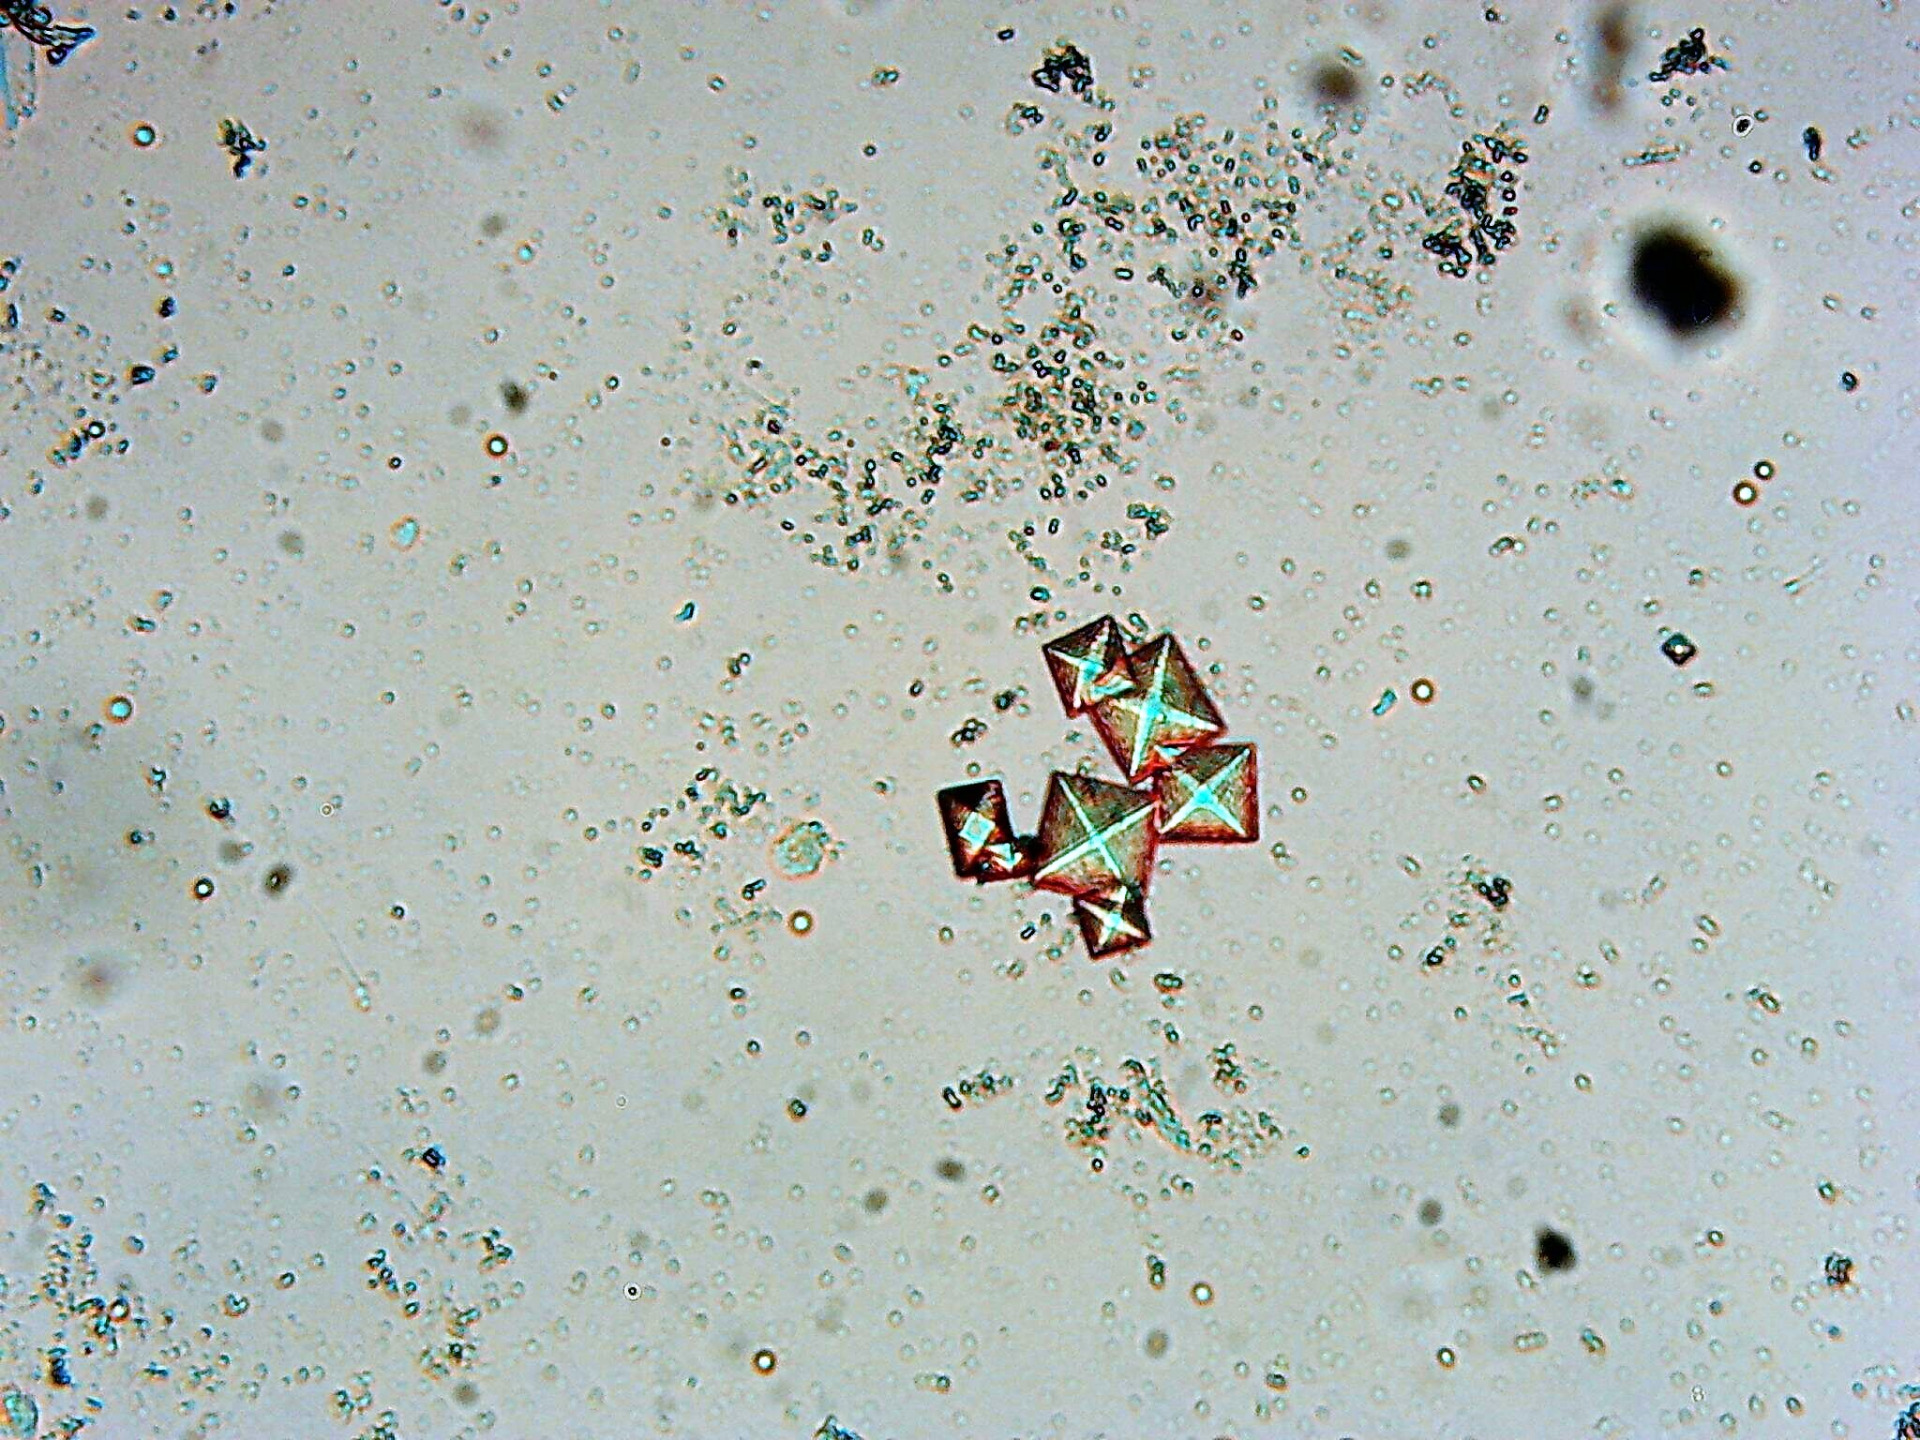

laboratórne vyšetrenie krvi, moču, trusu, cytológia